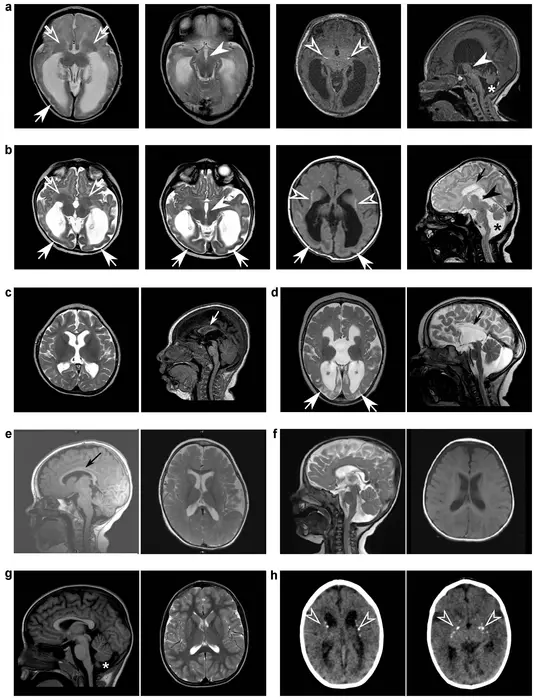

The scientists analyzed samples from Adeliade and 21 other people with the condition. By growing stem cells in a dish using the participants’ genetic code, the scientists found that mutations in a gene called DENND5A create disfunction, and this disfunction stops brain cells from dividing properly during development. The result is a developing brain with less stem cells, shortening the crucial time period that the brain forms as an embryo.